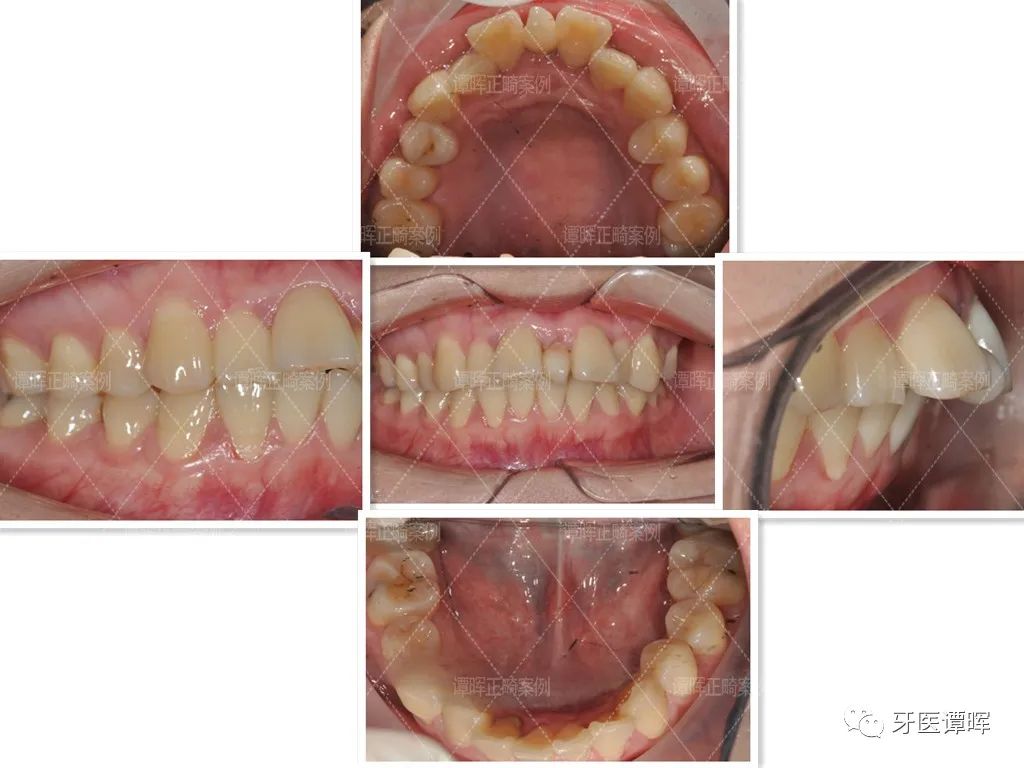

先看一下这位小姐姐的乱牙期:

矫正前

△牙齿正面照:牙齿轻度扭转,一个门牙高一个门牙底,上前牙就看着就很不齐,微微张嘴时整体面部曲线不是很好,可以感觉到嘴凸。

△从口内照可以看出,上颌牙不齐,并未排齐在牙弓上。前牙往舌侧倾斜,牙齿也不对称。